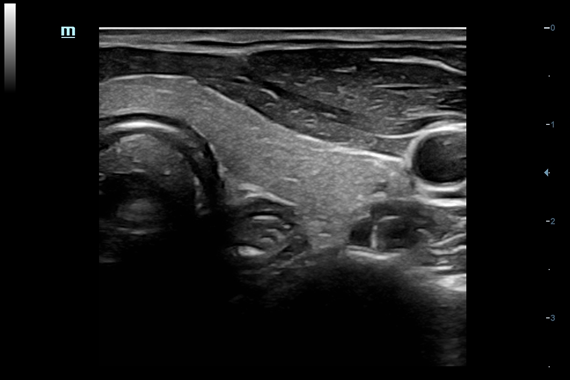

Система ультразвукового исследования Mindray DC-60 EXP X-INSIGHT является новейшей разработкой для проведения комплексных обследований на высшем уровне. Она обеспечивает решение самых сложных задач в таких областях, как кардиология, акушерство и гинекология, сосудистые заболевания, педиатрия и многие другие.

DC-60 EXP X-INSIGHT - это современный стационарный УЗИ-аппарат с функцией сенсорного управления и очищенной гармонической визуализацией, обеспечивающей лучшее контрастное разрешение и технологию 4D-визуализации. Он оснащен 21,5-дюймовым монитором, который может поворачиваться на 180 градусов, что удовлетворяет потребности врачей в качественной ультразвуковой диагностике.

• Внутриполостной датчик Mindray V11-3

• Ректально-вагинальный датчик Mindray V11-3B

• 3D/4D ректально-вагинальный датчик Mindray DE10-3E